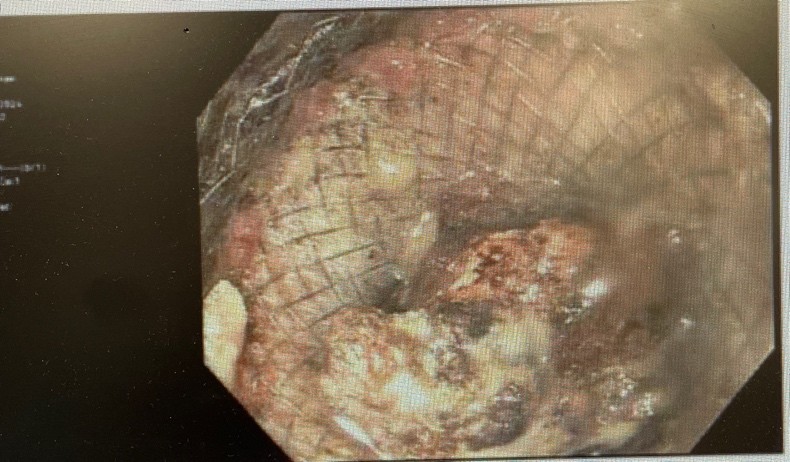

Figure 3. Necrotic tissue visualized through LAMS.

Figure 3